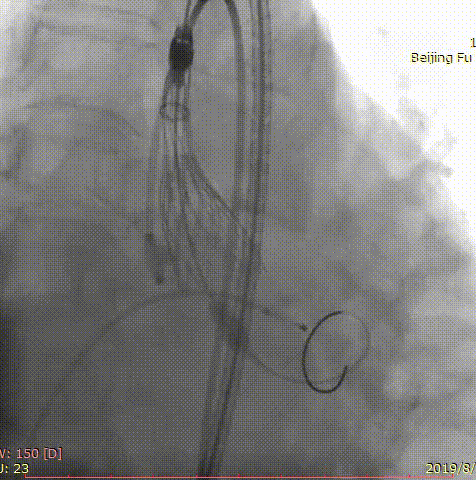

第三位患者是一位84岁女性,因间断头晕伴气短2年,加重1年入院,超声心动图提示主动脉瓣重度狭窄,左室壁肥厚,节段性室壁运动减低,主动脉瓣平均跨瓣压差91mmHg,收缩期流速 m/s,瓣口面积 0.6cm2。患者合并房颤、慢性肾功能不全、贫血。完善CT检查,测得主动脉瓣环 21*25mm,周长71.3mm,面积399.2mm2,患者三叶瓣,钙化分布较均匀,结合瓣上多平面分析方法,选择经左侧股动脉,应用微创心通 20*40mm敖广球囊预扩张,并成功植入Vitaflow 24mm主动脉瓣膜。术后超声提示收缩期流速1.7m/s,较术前明显下降。

术前影像